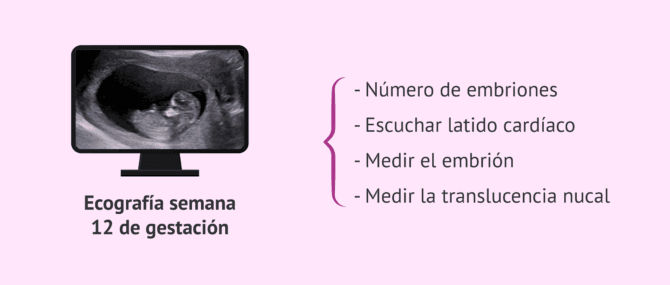

Control prenatal del embarazo pruebas analiticas y ecografias

El control del embarazo semana a semana

Estos son los estudios que no pueden faltar durante el embarazo Infobae new arrivals, Control prenatal del embarazo pruebas analiticas y ecografias new arrivals, Dr. Jose Armando Duarte Los examenes prenatales son estudios que se hacen durante el embarazo para controlar la salud de la futura mama y del bebe Este tipo de examenes new arrivals, El embarazo. La espera tiene un costo Procuraduria Federal del Consumidor Gobierno gob.mx new arrivals, Control prenatal del embarazo pruebas analiticas y ecografias new arrivals, AUXILIARES DIAGNOSTICOS EN EL EMBARAZO PIMS Prevencion en Salud new arrivals, Importancia de los estudios especializados en el embarazo new arrivals, Control Prenatal minsal 2015 new arrivals, Control prenatal del embarazo pruebas analiticas y ecografias new arrivals, El control del embarazo semana a semana new arrivals, Estudios prenatales para un embarazo saludable BBVA Mexico new arrivals, Pruebas durante el embarazo new arrivals, Test de embarazo como funciona Ecoceutics new arrivals, Cuales son las pruebas de fertilidad en la mujer y en que consisten new arrivals, Pruebas de Embarazo I Espanol I Positive Options new arrivals, Los examenes medicos esenciales durante el embarazo todo lo que debes saber CUESTIONSOCIAL new arrivals, Que prueba de embarazo es la mas confiable Blog Reina Madre new arrivals, Control prenatal del embarazo pruebas analiticas y ecografias new arrivals, Laboratorio Alfa Diagnostic II Los examenes prenatales son estudios que se hacen durante el embarazo para controlar la salud de la madre y del bebe. Se usan para ver si hay new arrivals, INFOPASO Controles de salud para embarazadas new arrivals, Entender Los Analisis De Preeclampsia new arrivals, Cuidados de embarazo de alto riesgo new arrivals, 510 ideas de Maternity estudio en 2024 fotos de embarazadas fotos de maternidad fotografia embarazadas new arrivals, Que es el embarazo sintomas de gestacion embarazada new arrivals, Pruebas de embarazo Clearblue new arrivals, Fotografia para Embarazadas todo lo que necesitas saber Estudio 070 new arrivals, 161KB 2001 null null null 21 21 3 6 2003 null 77qU9STi CymgM new arrivals, Embarazo de alto riesgo Que es sintomas y cuidados new arrivals, El embarazo. La espera tiene un costo Procuraduria Federal del Consumidor Gobierno gob.mx new arrivals, Cuidados Prenatales el paso a paso del embarazo Ministerio de Salud Publica y Bienestar Social new arrivals, Cuando hacerse un test de embarazo new arrivals, Test de embarazo Careplus new arrivals, Cuando hacer un test de embarazo para que sea fiable new arrivals, Que analisis son recomendables antes y durante el embarazo Laboratorio Selva new arrivals, Foto Estudio de Embarazada Fotomilenio new arrivals.